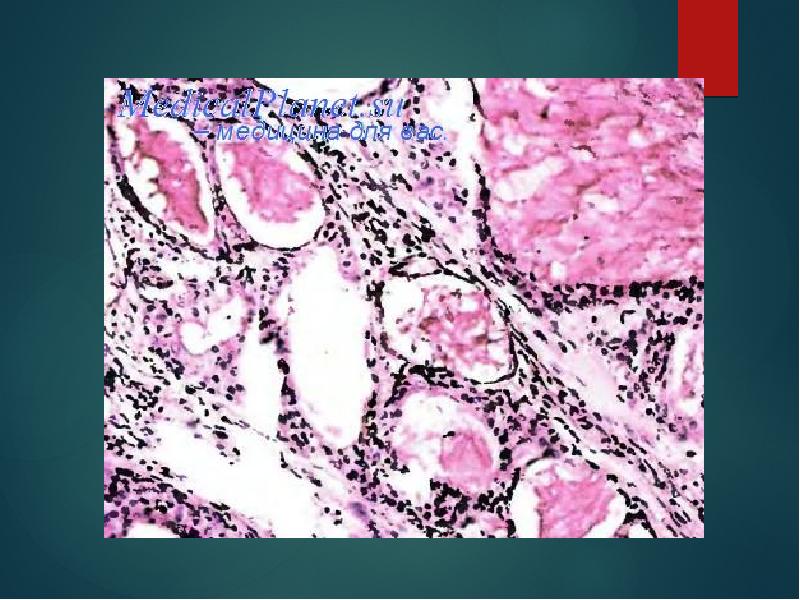

- 11. Микроскопически опухоль, кроме выраженной эпителиальной ткани, имеет в своем составе мезенхимоподобные

- 20. Макроскопически опухоль серо-белого цвета с мелкими полостями, заполненными слизью. Микроскопически она